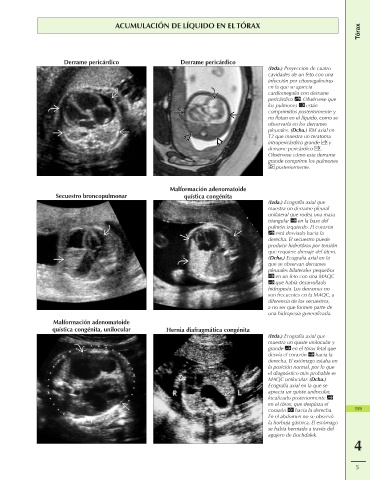

ACUMULACIÓN DE LÍQUIDO EN EL TÓRAX

Derrame pericárdico Derrame pericárdico

(Izda.) Proyección de cuatro

cavidades de un feto con una

infección por citomegalovirus

en la que se aprecia

cardiomegalia con derrame

pericárdico . Obsérvese que

los pulmones están

comprimidos posteriormente y

no flotan en el líquido, como se

observaría en los derrames

pleurales. (Dcha.) RM axial en

T2 que muestra un teratoma

intrapericárdico grande y

derrame pericárdico .

Obsérvese cómo este derrame

grande comprime los pulmones

posteriormente.

Malformación adenomatoide

Secuestro broncopulmonar quística congénita

(Izda.) Ecografía axial que

muestra un derrame pleural

unilateral que rodea una masa

triangular en la base del

pulmón izquierdo. El corazón

está desviado hacia la

derecha. El secuestro puede

producir hidrotórax por tensión

que requiere drenaje del útero.

(Dcha.) Ecografía axial en la

que se observan derrames

pleurales bilaterales pequeños

en un feto con una MAQC

que había desarrollado

hidropesía. Los derrames no

son frecuentes en la MAQC, a

diferencia de los secuestros,

a no ser que formen parte de

una hidropesía generalizada.

Malformación adenomatoide

quística congénita, unilocular Hernia diafragmática congénita

(Izda.) Ecografía axial que

muestra un quiste unilocular y

grande en el tórax fetal que

desvía el corazón hacia la

derecha. El estómago estaba en

la posición normal, por lo que

el diagnóstico más probable es

MAQC unilocular. (Dcha.)

Ecografía axial en la que se

aprecia un quiste unilocular,

localizado posteriormente

en el tórax, que desplaza el

corazón hacia la derecha. 159

En el abdomen no se observó

la burbuja gástrica. El estómago

se había herniado a través del

agujero de Bochdalek.